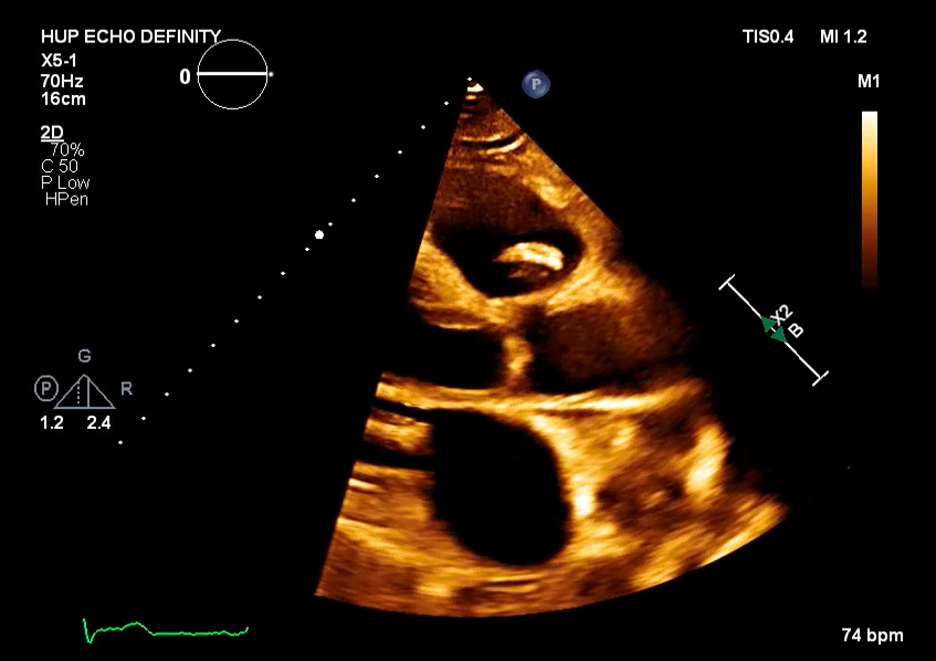

Case Presentation: 61-year-old man with coronary artery disease, tobacco use, and partial R toe amputation after trauma presented to an outside hospital with 3 months of fevers, night sweats, and 30 kg weight loss. He was found to have pancytopenia, splenomegaly, and retroperitoneal lymphadenopathy raising concern for malignancy. These findings prompted a bone marrow biopsy which showed trilineage hyperplasia without evidence of hematological or metastatic neoplasm. Extensive coronary calcifications were incidentally noted on imaging. He was discharged with plan for Hematology and Cardiology follow-up. He presented to our hospital with persistent symptoms. On exam, he was febrile to 39.2C, tachycardic, and had a 3/6 holosystolic murmur at the apex. Labs showed pancytopenia with WBC 4.5, hemoglobin 8, and platelets 47K. Blood cultures were obtained and vancomycin, cefepime, and azithromycin were administered. In less than 24 hours, blood cultures returned positive for streptococcus parasanguinis and antibiotics were narrowed to ceftriaxone. Transthoracic and transesophageal echocardiograms demonstrated a large (1.4 x 0.6 cm) pulmonic valve vegetation with severe pulmonic valve regurgitation and ruptured posterior mitral valve leaflet chordae with severe mitral valve regurgitation. The size of the vegetations and degree of valvular dysfunction prompted urgent surgical consultation and he subsequently underwent pulmonic and mitral valve replacement with concurrent coronary artery bypass grafting for high grade right coronary artery stenosis. Intraoperative exam demonstrated large pulmonic valve vegetations and bi-leaflet mitral valve vegetations. Withing 72 hours of antibiotic initiation, he reported clinical improvement with resolution of fevers and night sweats and improvement in his appetite and energy level and subsequently completed a 6-week course of ceftriaxone. Interestingly, during his admission to our hospital, his prior bone marrow biopsy was reviewed and found to be suggestive of low-grade myelodysplastic syndrome (MDS). On most recent laboratory testing, obtained at completion of antibiotics, he remains mildly pancytopenic.